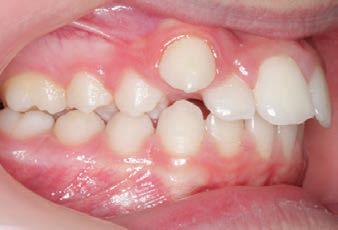

CLASS II DIV.1 - Marra

INITIAL - 4/4/18

PROGRESS 1 - 26/9/18 - Class I platform accomplished in 5.75 months with Motion 3D COLOR Appliance

PROGRESS 2 - 26/9/18 - Placement of the SLX 3D Clear Brackets